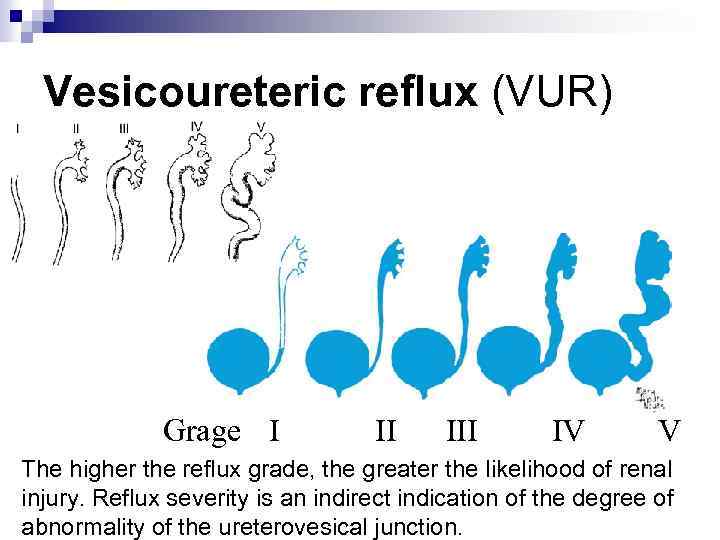

Vesicoureteric reflux (VUR) Reflux severity is graded using the International Reflux Study Classification of I to V and is based on the appearance of the urinary tract on a contrast voiding cystourethrogram (VCUG).

Vesicoureteric reflux (VUR) Reflux severity is graded using the International Reflux Study Classification of I to V and is based on the appearance of the urinary tract on a contrast voiding cystourethrogram (VCUG).

Vesicoureteric reflux (VUR) G Grage I II IV V The higher the reflux grade, the greater the likelihood of renal injury. Reflux severity is an indirect indication of the degree of abnormality of the ureterovesical junction.

Vesicoureteric reflux (VUR) G Grage I II IV V The higher the reflux grade, the greater the likelihood of renal injury. Reflux severity is an indirect indication of the degree of abnormality of the ureterovesical junction.